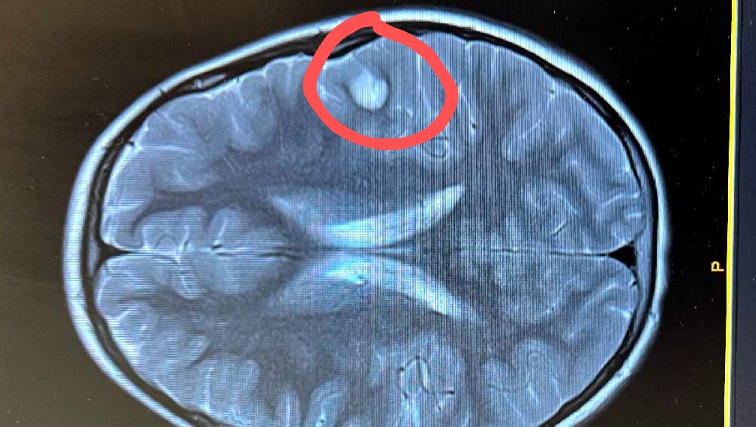

On April 23, 2025, I received the news no parent wants to receive. The MRI had shown a clear lesion/tumor on the left side of Myka's brain.

Myka has since undergone another MRI with contrast and brain mapping to learn what brain functions the lesion may be affecting. She has been on seizure medication since the discovery and has been very brave.

On May 2, 2025, we received the second MRI with contrast results. We received both relieving and stressful updates. The results showed three possible diagnoses: Astrocytoma, Pleomorphic Xanthoastrocytoma, or Ganglioglioma.

The relieving news is that all three current possible diagnoses are benign lesions. The stressful news is that the primary treatment is surgical removal for all three possible diagnoses.

Myka will be undergoing surgery to remove the lesion on May 28th. She's being very brave and has named her lesion "Billy." Her surgeon has a very optimistic outlook.